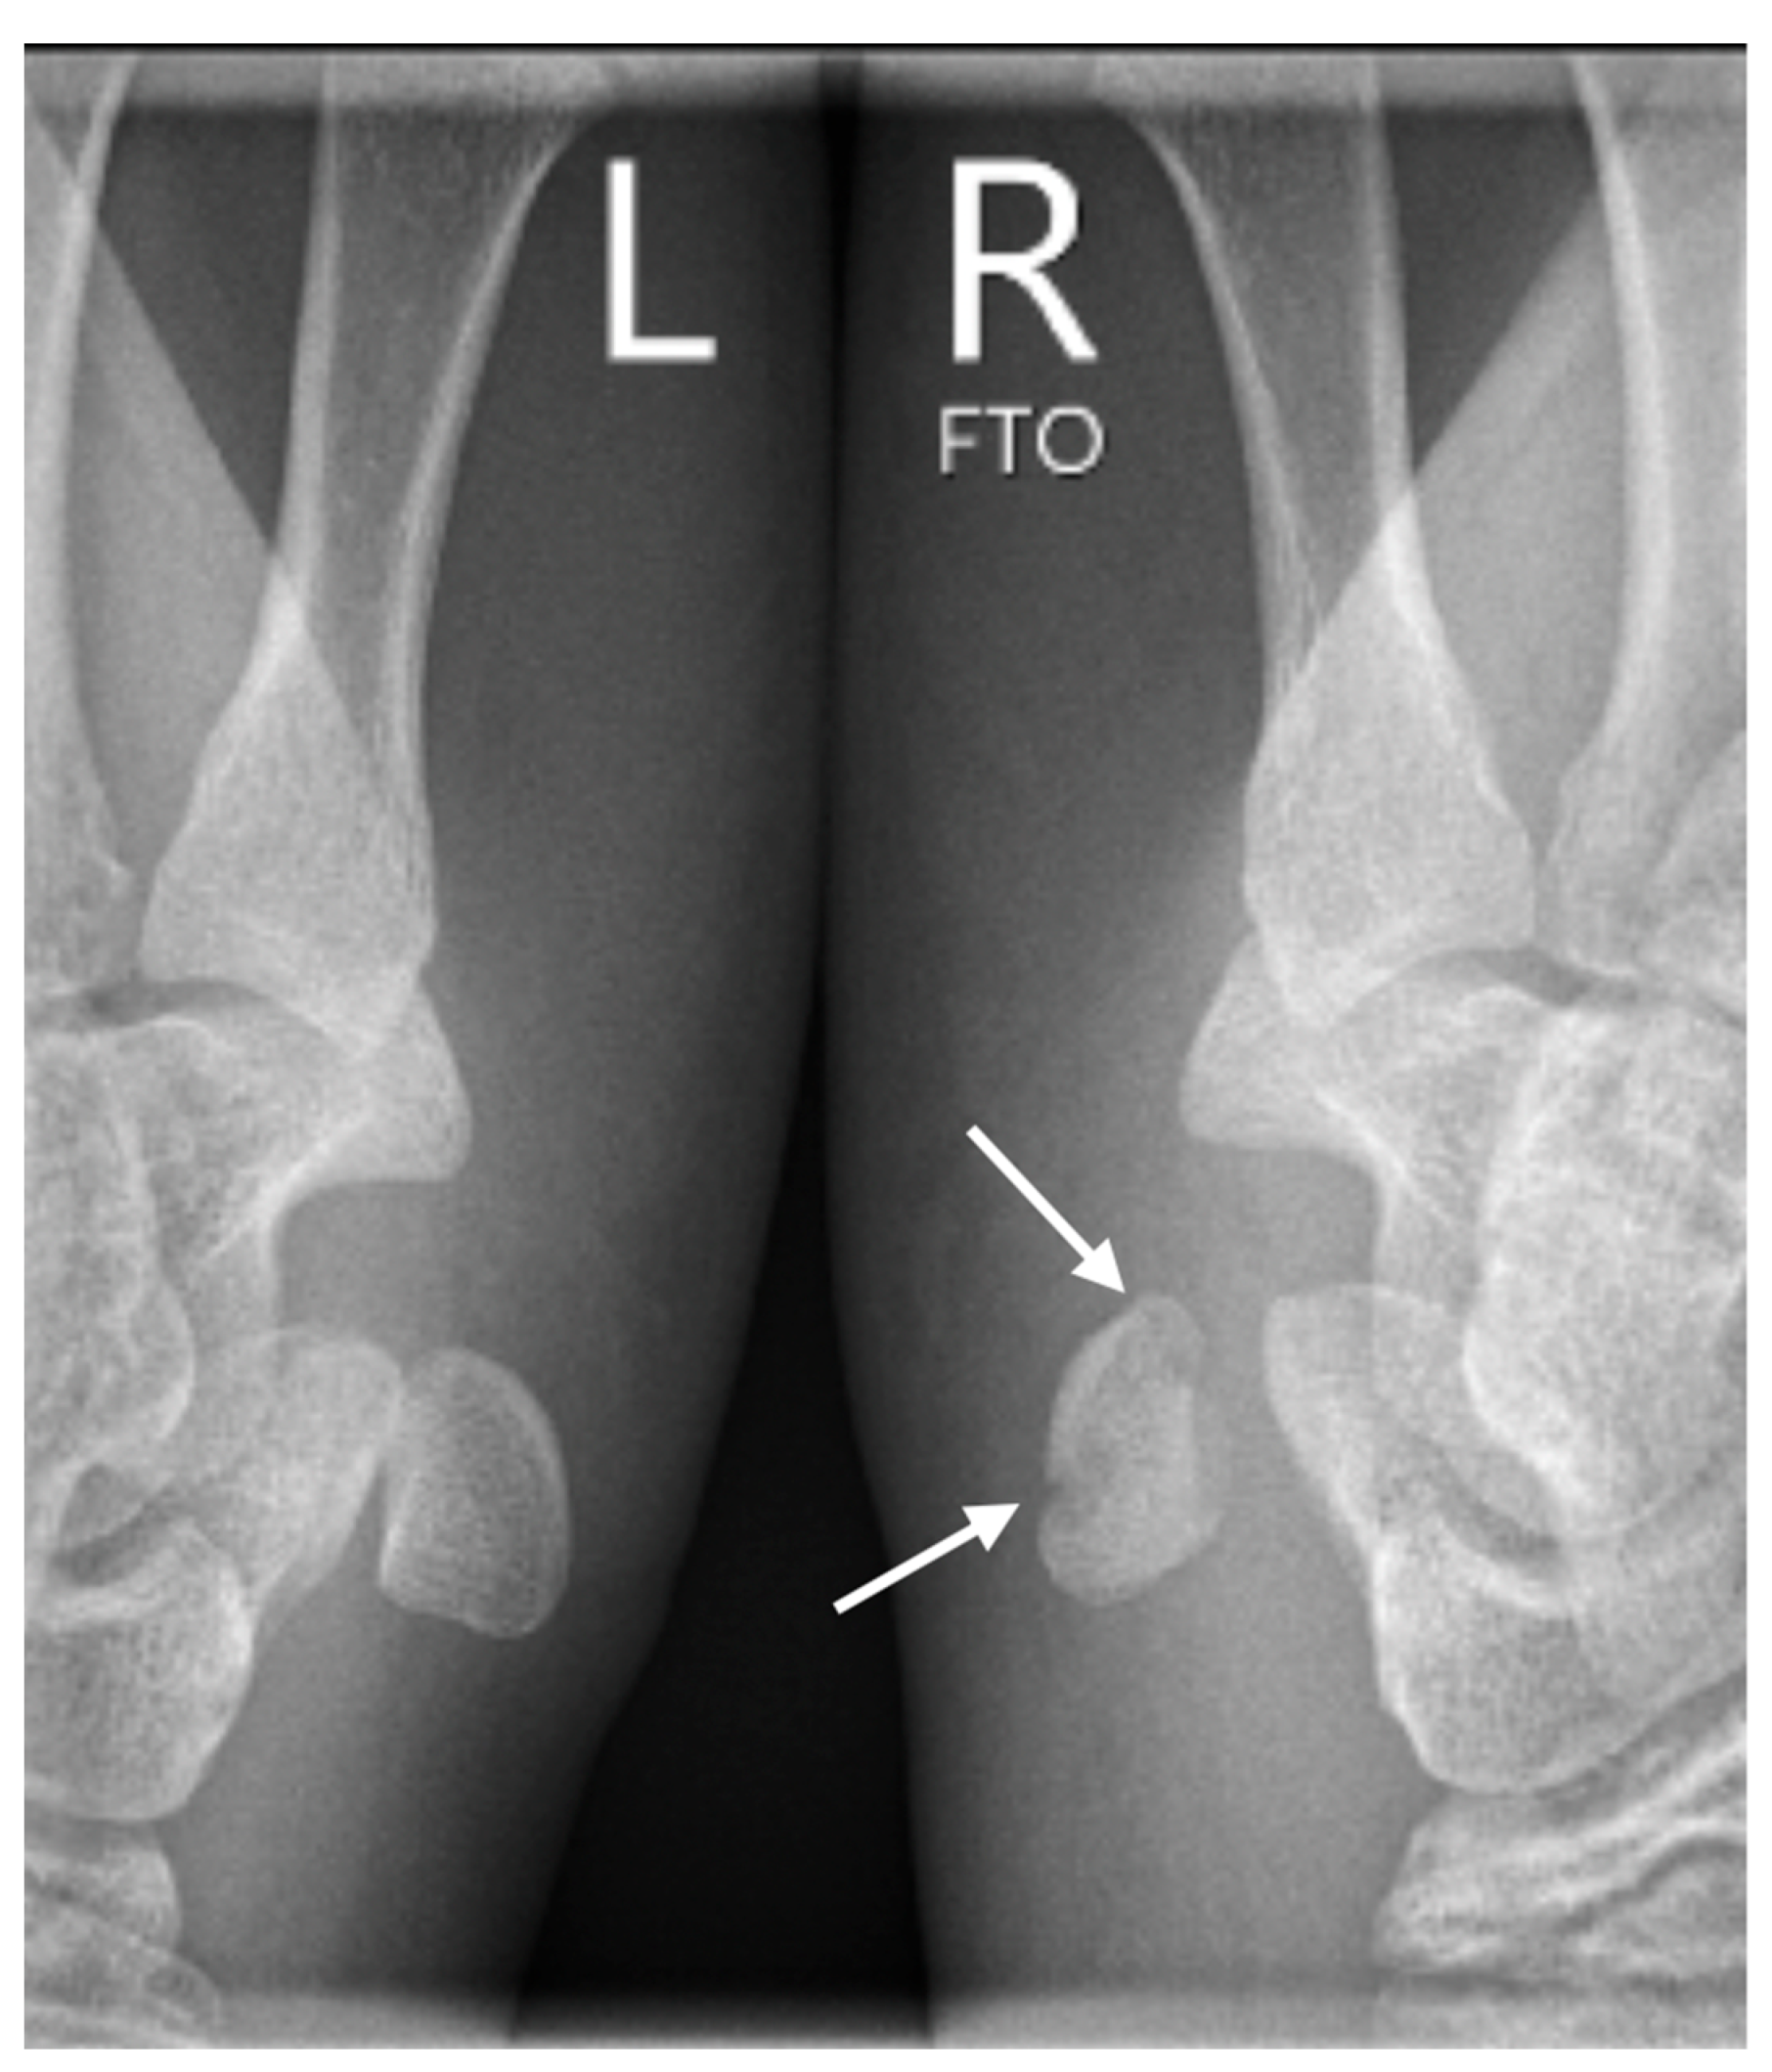

Further confirmation of the dislocation was obtained through subsequent conventional radiographs, specifically utilizing the semi-supination oblique view in a 30° angle (pisiform, pisotriquetral view), with side-by-side comparison of both wrists (Figure 3).

Figure 3.

The semisupination oblique X-ray in 30° angle, side-by-side comparison (L: left, R: right), showing a non-displaced fracture of the pisiform bone (white arrows).

The primary challenge lies in diagnosis, as changes on X-rays are often subtle or absent in pisiform bone injuries. Fractures of PJ may go unnoticed, especially in patients younger than 7.5 years old, largely due to the absence of the ossification center [18]. Hence, a CT scan may be necessary for accurate assessment. Typically, these injuries coincide with more severe fractures or soft tissue damage, with diagnosis guided by the predominant issue. In our case, the pisiform fracture or dislocation was incidentally revealed during diagnostic evaluation for the primary concern. Due to suspicion of a concurrent dislocation of the PTJ, we conducted additional X-rays of both PTJ’s for a side-by-side comparison as a reference (Figure 4).